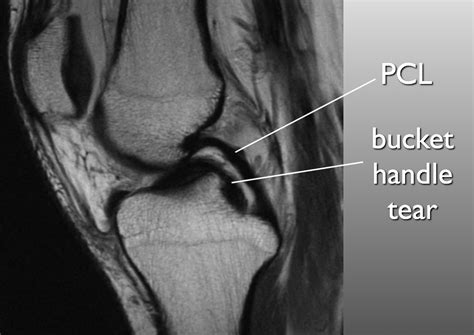

Web double pcl sign. Web double pcl sign double anterior horn sign. We undertook this study to assess the presence of a double pcl sign and its correlation with arthroscopic findings. Web the body of the medial meniscus is discontinuous and diminutive posteriorly with excess meniscal tissue at the intercondylar fossa parallel to the sagittal plane simulating the double pcl sign, consistent with a bucket handle tear. Web gross anatomy the posterior cruciate ligament arises from the lateral surface of the medial femoral condyle and inserts onto the posterior lateral intercondylar surface of the tibial plateau 4. 1 article features images from this case Pain with valgus stress at 30° knee flexion, which isolates the superficial mcl. The ligament is intracapsular but extrasynovial and is, on average, 38 mm in length and 13 mm in width. Web double pcl sign is a highly specific indicator of displaced bucket handle meniscal tear. The body of the medial meniscus is discontinuous and diminutive posteriorly with excess meniscal tissue at the intercondylar fossa parallel to the sagittal plane simulating the double pcl sign, consistent with a bucket handle tear.

Pain with valgus stress at 30° knee flexion, which isolates the superficial mcl. Gapping of medial joint line. The body of the medial meniscus is discontinuous and diminutive posteriorly with excess meniscal tissue at the intercondylar fossa parallel to the sagittal plane simulating the double pcl sign, consistent with a bucket handle tear. Web double pcl sign double anterior horn sign. Meniscal extrusion or ghost sign, may indicate meniscal root tear. Web gross anatomy the posterior cruciate ligament arises from the lateral surface of the medial femoral condyle and inserts onto the posterior lateral intercondylar surface of the tibial plateau 4. Web double pcl sign is a highly specific indicator of displaced bucket handle meniscal tear. Web the body of the medial meniscus is discontinuous and diminutive posteriorly with excess meniscal tissue at the intercondylar fossa parallel to the sagittal plane simulating the double pcl sign, consistent with a bucket handle tear. The ligament is intracapsular but extrasynovial and is, on average, 38 mm in length and 13 mm in width. Pain with valgus stress at 30° knee flexion, which isolates the superficial mcl. We undertook this study to assess the presence of a double pcl sign and its correlation with arthroscopic findings.